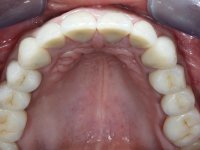

Foi proposto ao paciente fazer uma reabilitação total com infraestruturas em zircónia revestidas a cerâmica. No maxilar superior, seriam realizadas 6 coroas (1.3/1.2/1.1/2.1/2.2/2.3), uma ponte de 3 elementos (1.4/1.5/1.6) e uma ponte de 4 elementos (2.4/2.5/2.6 e 2.7). No maxilar inferior, foram propostas 7 coroas (4.3/4.2/4.1/3.1/3.2/3.5 /3.6) e duas pontes (4.4//4.5/4.6) e (3.3/3.4#/3.4).O objetivo seria subir a D.V.O., descruzar a mordida do lado direito, eliminar as infiltrações e as exposições radiculares e reabilitar o paciente com estruturas protéticas com aspeto mais natural.